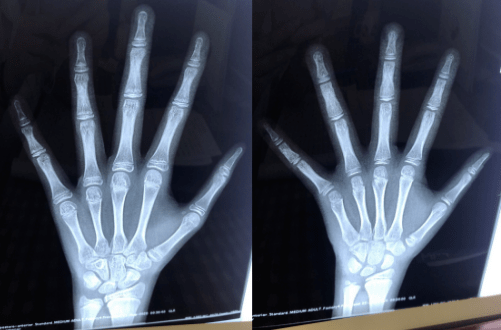

骨龄是什么?如果孩子生长发育出现问题,我们多久测一次骨龄合适呢?让我们一起来科普了解 一下。

骨龄,即为骨骼年龄,骨龄代表着发育年龄,可根据X光片的特定图像确定。

骨龄能准确地反映孩子骨骼的成熟度,如果骨龄和孩子年龄相差超过1岁,孩子有可能会发育迟缓,或者发育过快,都会影响到孩子的终身高。相比于年龄,骨龄更能准确地反映孩子骨骼的成熟度,是评估儿童体格发育情况的良好指标。

一般3周岁以后的孩子,你觉得身高偏矮就可以到医院测一下骨龄,青春期前孩子一般一年测一次骨龄,青春期以后一般是6个月测一次,甚至3-4个月就可以测一次,因为青春期孩子由于性激素作用,骨龄会进展比较快。如果你孩子处于生长激素治疗或性早熟的治疗过程中,根据具体情况定期监测骨龄。